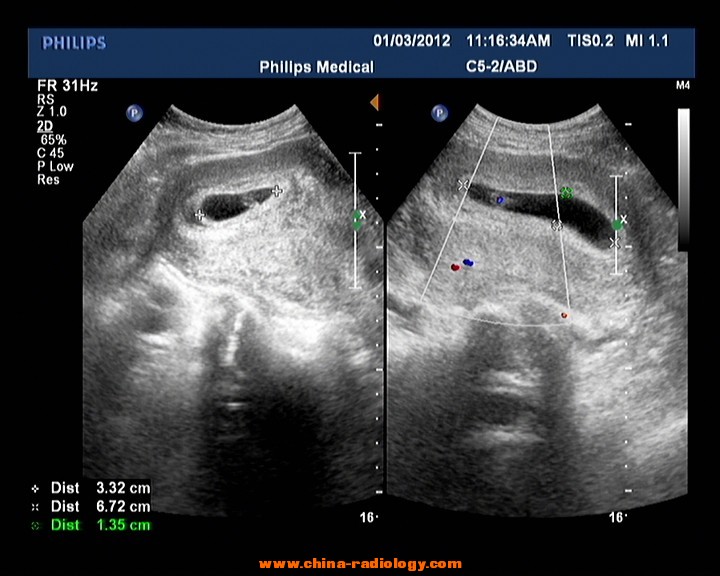

2.孕6周时出现胎心搏动,有胎芽,就像是一颗种子才刚刚发芽一样。